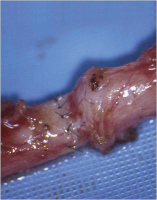

Refertilisierung und ICSI bei obstruktiver Azoospermie

Journal für Reproduktionsmedizin und Endokrinologie - Journal of Reproductive Medicine and Endocrinology 2010; 7 (5): 408-412 Volltext (PDF) Summary Praxisrelevanz Abbildungen